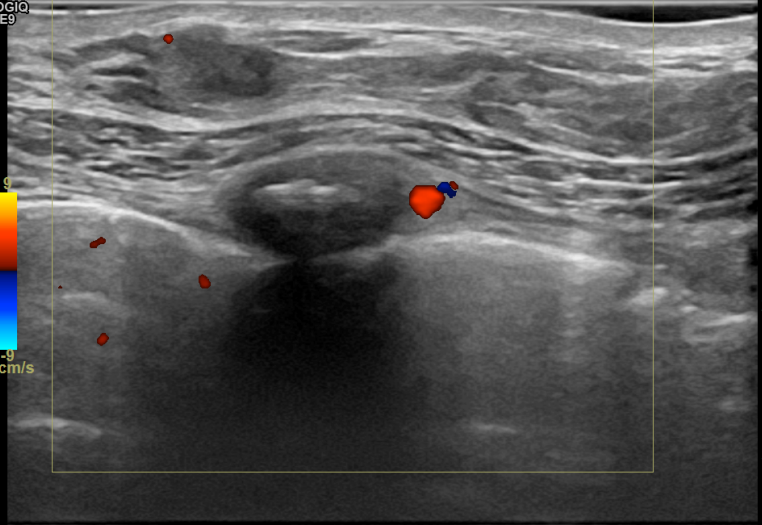

상기환자는 만져지는 멍울로 내원하신 60대후반

여성분으로 의심스러운 우측혹 조직검사 시행해 침윤성암 으로 진단되었습니다